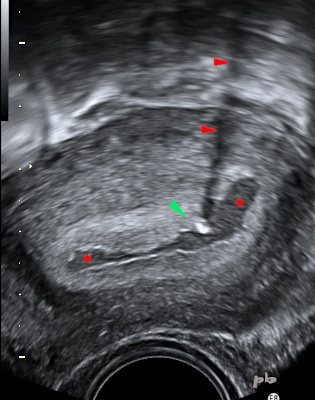

7-GEU

-

Hématométrie (★).

-

Dans la cavité, présence d’une zone hyperéchogène (►), avec cône d’ombre (►) : stérilet.

-

Caduques hyperéchogènes bordant la cavité.

-

Ne pas oublier que les DIU ne protègent que des grossesses intra-utérines.